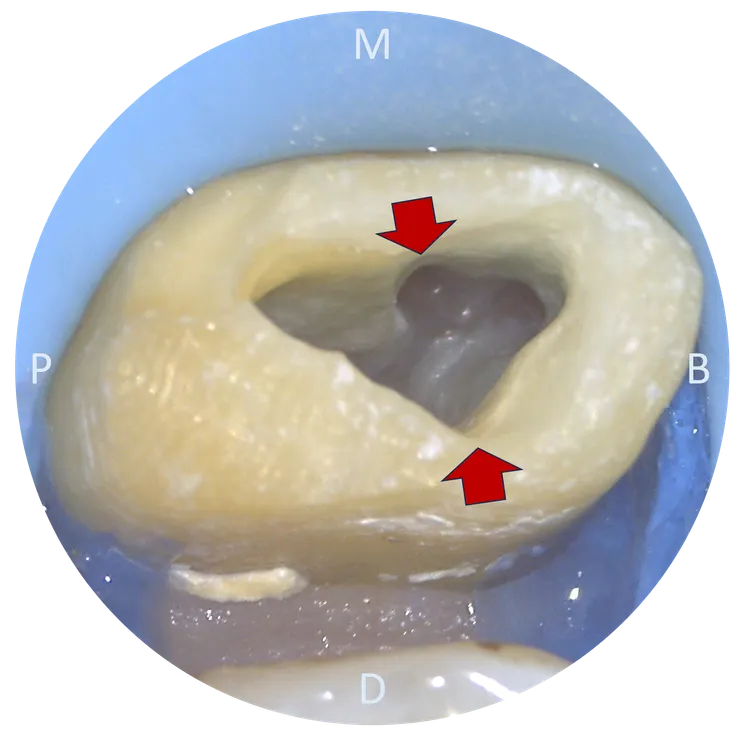

完成初步的 access cavity 後,可以看到 mesial wall 有非常突出的 dentin shelf 蓋住底下的 chamber floor.

車掉那片 dentin shelf 後,露出了 chamber floor.

此時隱約可以看到 P, DB, MB orifices.

繼續把 mesial wall 的 undercut 修掉, MB2 orifice 就顯露出來了。

圖中箭頭所指的,就是我為了保護脆弱的 danger zone 而適度犧牲掉的部分 pericervical dentine 以及 contralateral wall.就這樣試著把 file 督進去......